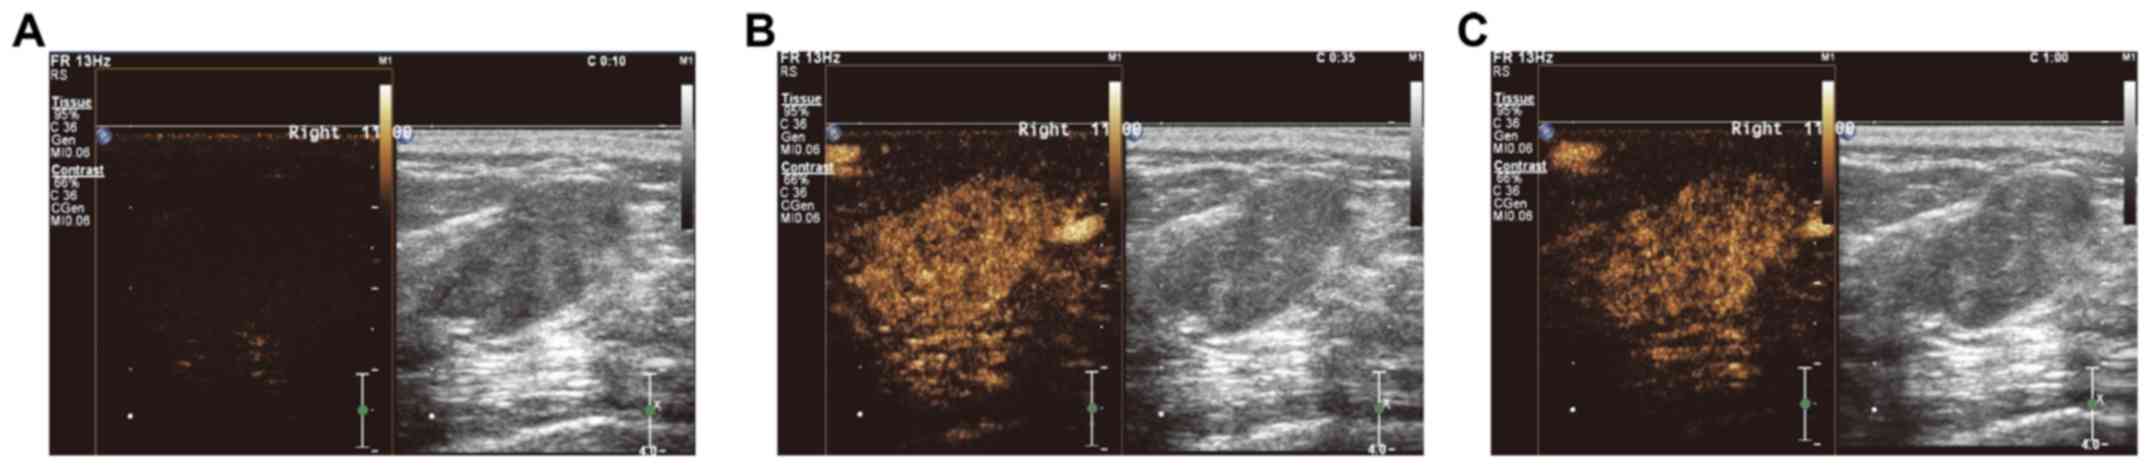

Clinical value and application of contrast-enhanced ultrasound in the differential diagnosis of malignant and benign breast lesions

The aim of the present study was to assess the performance of contrast-enhanced ultrasound in distinguishing between malignant and benign breast lesions and the diagnostic value of its clinical application. A total of 52 cases with malignant breast tumors and 73 cases with benign breast lesions were included in the study. Time-intensity curves (TICs) for contrast-enhanced ultrasound were recorded, and the perfusion parameters were obtained and analyzed. Typical features of malignant breast tumors included irregular shape and vascular morphology, uneven contrast agent distribution, filling defects and contrast agent retention, ‘fast-out’ wash-out mode, unclear boundaries and uneven internal echo. Benign lesions were characterized by ‘slow-out’ or synchronous wash-out mode. Regarding perfusion, the starting time of the perfusion of the Sone-Vue microbubble contrast (always 20-30 sec) and time to peak (TTP) were significantly earlier for the malignant lesions, while the wash-out time was later. A significantly greater peak intensity, rising slope and area under the TIC were observed for the malignant breast lesions. All of the malignant breast lesions exhibited an enlarged focus scope on ultrasound, while no obvious focus scope enhancement was observed for benign breast lesions. Furthermore, the TICs of 88.4% of malignant breast lesions were of the fast-rising and slow-declining type, while the TICs of 75.3 and 17.8% of the benign breast lesions were of the slow-rising and fast-declining, and fast-rising and fast-declining type, respectively. Receiver operating characteristics analysis indicated that the TTP, wash-out time and rising slope might contribute to the differential diagnosis between malignant and benign breast lesions. In conclusion, TIC parameters of contrast-enhanced ultrasound have promising clinical value in differentiating between malignant and benign breast lesions. The TTP, wash-out time and rising slope may contribute to the diagnosis of patients with breast lesions to facilitate timely treatment and prognostication of breast cancer patients.